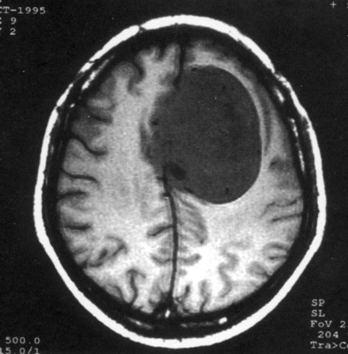

问题 病历摘要:??患者,男,40岁。发作性左下肢抽搐1年余,每次发作3~5分,每周发作1~2次。每次发作后感左下肢乏力,约半日后可自行恢复。既往身体健康。体检:神清,头顶部偏右有局限性骨性隆起(1.5×1.5cm),左鼻唇沟稍浅,伸舌居中。感觉、运动无明显异常。左浅反射减退,左下肢腱反射稍亢进,左Babinski征(-)。 下列关于脑膜瘤的叙述哪些是错误的?